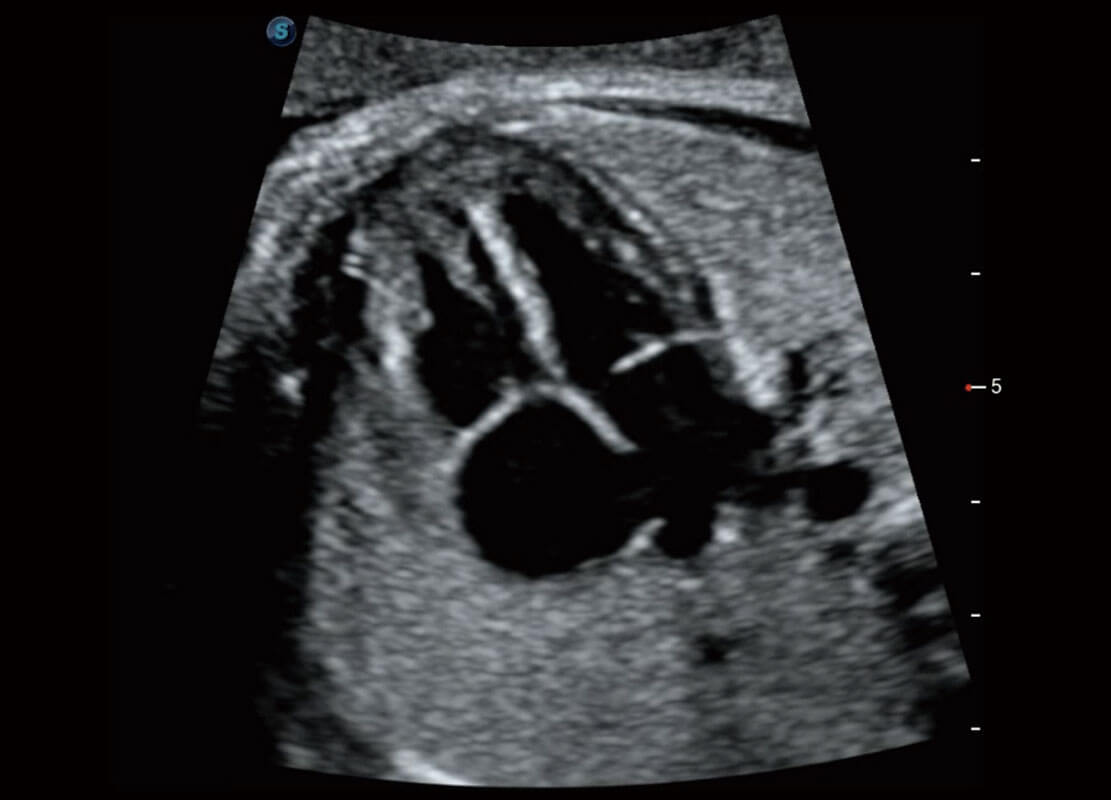

右室双出口